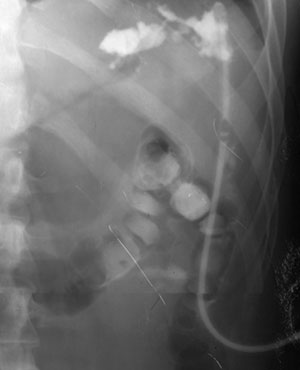

Рис. 1. По дренажной трубке в свищевой ход введено контрастное вещество (Слева). В толстую кишку (per rectum) введен воздух (Справа). В просвете толстой кишки определяется контраст, что свидетельствует о наличии толстокишечного свища.